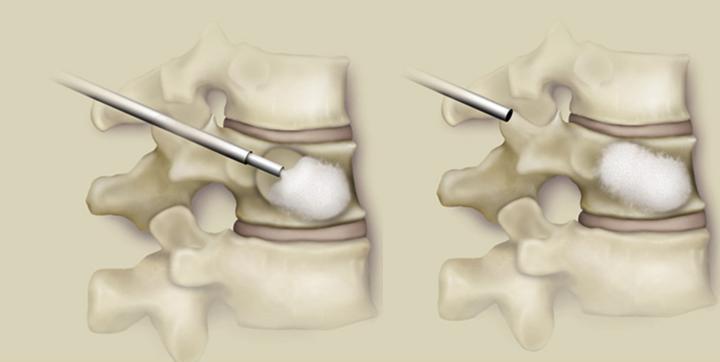

To μπαλονάκι φουσκώνει προοδευτικά ανατάσσοντας το κάταγμα,όπως φαίνεται στη μεσαία εικόνα και αποσύρονται αφήνοντας την νεοδημιουργειθήσα κοιλότητα:

Μέσα από την κάνουλα εγχύεται τσιμέντο μέχρι να πληρωθεί η κοιλότητα και τελικά αποσύρουμε την κάνουλα.